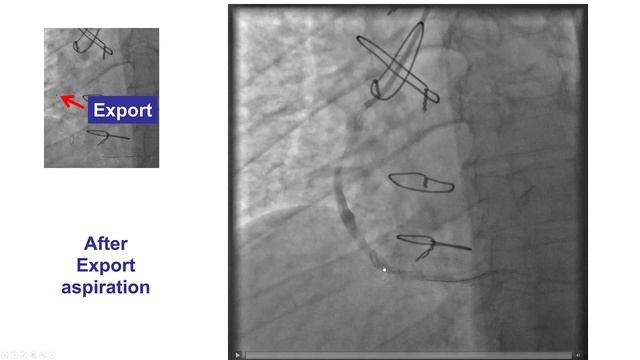

Case 38: PCI Manual: No Reflow During SVG PCI